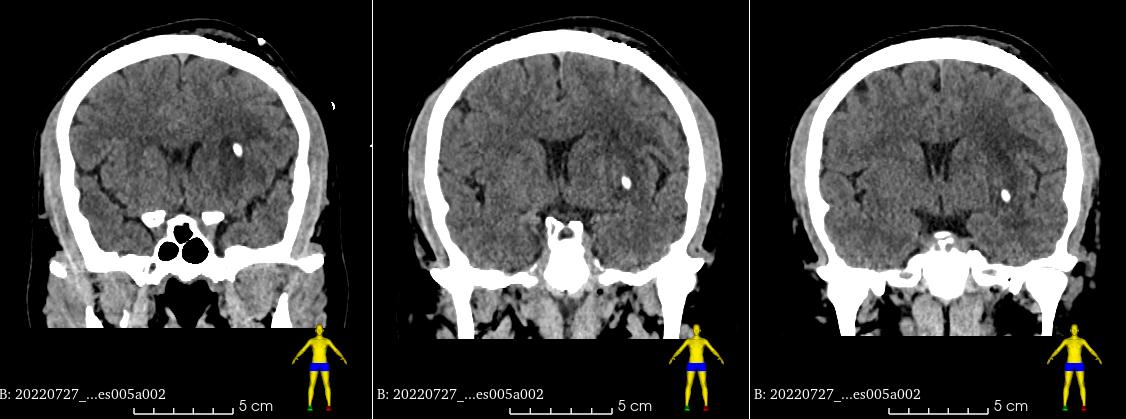

术后复查CT,置管精准       “激光定位技术为现代数字外科技术的一部分,以强大的精准定位技术应用于稳定血肿的穿刺治疗,并取得良好的临床效果。”据神经外二科主任朱英杰介绍:通过三维重建血肿、神经、骨性及头皮等标志,多维度了解颅内的病变结构与个体差异,根据手术需要,通过数字技术,精细设计个性化的手术方案,测量各项定位数值,然后辅以激光定位穿刺,与传统的经验性手术相比,该技术能大大提高手术的精准度并减轻患者的手术创伤,最终使患者更快更好地康复。

靶向精准穿刺置管、引流通畅

术后复查CT,置管精准